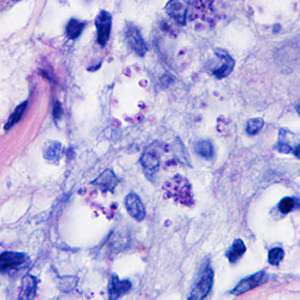

A 41-year-old woman presented to her health care provider with ulcerative lesions on her left ear and neck. Travel history included an excursion along the Amazon River in Brazil four months prior. She also reported numerous insect bites during her trip. The woman was referred to an infectious disease doctor who obtained a biopsy specimen from the largest lesion. The specimen was sent to Pathology where it was sectioned and stained with Giemsa. Figures A and B show what was observed at 1000x magnification. What is your diagnosis? Based on what criteria? What, if any, other testing would you recommend?

Figure A